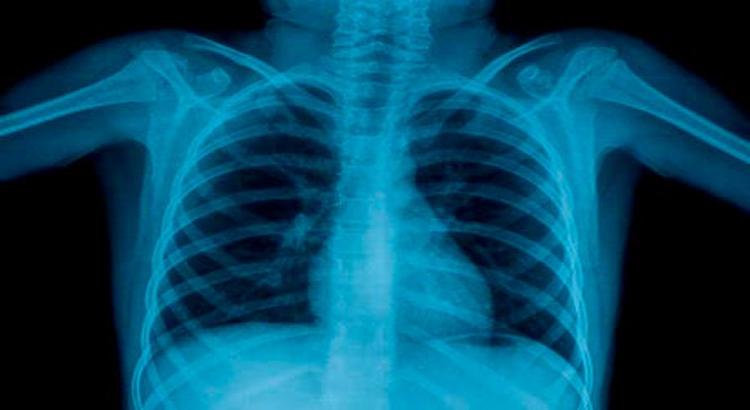

Alimlər insanın bioloji yaşını təyin etmək üçün döş qəfəsinin rentgen şüalarını oxuya bilən süni intellekt (AI) modeli hazırlayıb. Yaponiyanın Osaka Metropolitan Universitetinin tədqiqatçıları müəyyən ediblər ki, süni intellektin proqnozlaşdırdığı yaş insanın həqiqi yaşı ilə müqayisədə nə qədər çox olarsa, fərdlərin xroniki xəstəliyə tutulma ehtimalı bir o qədər yüksəkdir. Tədqiqatın müəlliflərindən olan Yasuhito Mitsuyamanın sözlərinə görə, nəticələr göstərir ki, döş qəfəsinin rentgenoqrafiyasına əsaslanan görünən yaş xronoloji yaşdan kənarda sağlamlıq vəziyyətini dəqiq şəkildə əks etdirməyə qadirdir. Xroniki xəstəliklərin şiddətini, gözlənilən ömür müddətini və mümkün cərrahi ağırlaşmaları proqnozlaşdırmaq üçün tətbiq daha da inkişaf etdiriləcək.

Tədqiqatçılar döş qəfəsinin rentgenoqrafiyasını və ya rentgen şüalarını oxuya bilən süni intellekt modeli yaratmaq üçün sağlam fərdlərdən alınan 67 min döş qəfəsinin rentgenoqrafiyasından istifadə ediblər. Sağlam fərdlər üçün süni intellektin təxmin etdiyi yaş ilə insanın xronoloji yaşı arasında güclü korrelyasiya əldə olunub. Onlar, həmçinin məlum xəstəlikləri olan insanların döş qəfəsinin 34 mindən çox rentgenoqrafiyasını sınaqdan keçiriblər. Süni intellektin proqnozlaşdırdığı bu tətbiqin hipertoniya, xroniki obstruktiv ağciyər, qaraciyər və xroniki böyrək çatışmazlığı kimi bəzi xəstəliklər üçün insanın həqiqi yaşı ilə müqayisədə daha yüksək yaş verdiyi təsbit edilib. Ancaq pnevmoniya kimi kəskin xəstəliklər üçün korrelyasiya daha aşağı olub. Bu nəticə o deməkdir ki, süni intellekt döş qəfəsinin rentgenoqrafiyasında kəskin deyil, xroniki dəyişiklikləri ələ keçirir, bu ağlabatandır, çünki yaşlanma zamanla yığılan xroniki dəyişikliklərin nəticəsidir.

Alimlərin fikrincə, bu süni intellekt modeli yaşa bağlı xəstəliklərin göstəricisi ola, erkən diaqnoz və müdaxiləyə kömək edə bilər.